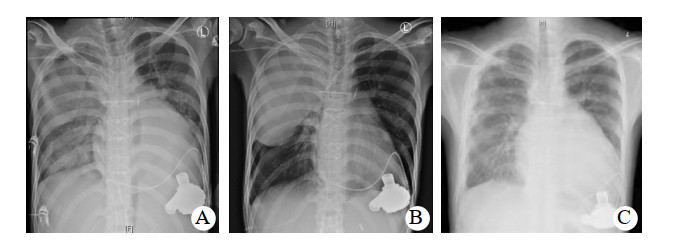

入ICU后查体:血压82/67 mmHg,心率120次/min, 体温36.5℃,呼吸12次/min。双侧瞳孔等大等圆,对光反射迟钝;口唇无发绀,双侧呼吸音粗糙,未闻及干湿啰音。监护提示:窦性心律,心律齐。心前区未闻及心脏杂音;腹平软,肝肋下未触及,肠鸣音弱。四肢末梢皮温正常,足背动脉搏动可及。留置纵隔、心包引流管。入科后即给予了呼吸机辅助呼吸,通气模式采用SIMV/PSV,压力支持12 cmH2O(1 cmH2O=0.098 kPa),呼吸频率12次/min,呼气末正压5 cmH2O, FiO2 0.5,给予舒芬太尼联合右美托咪定镇痛镇静治疗,应用头孢呋辛钠预防切口感染治疗,应用肝素和华法林钠抗凝治疗以及营养支持等综合支持治疗,患者循环稳定,胸片肺淤血较术前减轻,痰不多,于术后第4天顺利脱机拔管,拔管后自主呼吸稳定,少量白稀痰,胸片未见明显变化。术后第7天患者出现体温升高,最高体温38.5℃,痰量增多,为白粘痰,痰中带血,双肺听诊散在痰鸣音,脉搏氧饱和度下降至90%,血气分析提示PaCO2 42 mmHg,PaO2 59 mmHg,实验室检查,PCT 77.87 ng/mL,CRP 198.5 mg/L,患者血压下降,伴有少尿,胸片提示肺感染,经多学科会诊后除外其他部位感染,考虑患者术后合并重症肺炎、呼吸衰竭、感染性休克、急性肾损伤,遂给予再次气管插管机械通气治疗。同时为充分引流痰液,给予了俯卧位通气联合支气管镜肺泡灌洗治疗(俯卧位时间为每次12 h,支气管镜肺泡灌洗每日1次,灌洗剂量为生理盐水100 mL/次),并经验性应用美罗培南联合万古霉素抗感染治疗,给予了液体复苏及CRRT治疗、综合支持治疗。为维持血泵正常运转,继续华林钠口服抗凝治疗,维持INR 2.0~2.5。术后第8天痰培养和血培养均报告为耐碳青霉烯肺炎克雷伯菌,抗生素更改为头孢他啶- 阿维巴坦抗感染治疗。并于术后第15天给患者进行了气管切开治疗。头孢他啶阿维巴坦共应用17 d,期间患者因同时合并了肺部屎肠球菌、热带假丝酵母菌感染,根据药敏实验结果分别给予了替加环素、卡泊芬净等抗感染治疗。因此患者术前反复心衰,营养状况差;术后长期应用抗生素,加上体外循环的打击,机体免疫力差;术后第27天出现菌群失调,严重腹泻,粪便球杆比9 ∶ 1,化验为艰难梭菌感染,给予静脉万古霉素口服(125 mg,q6h)治疗,同时停用所有抗生素。因患者感染未完全控制,继续给予了俯卧位通气联合支气管镜肺泡灌洗治疗,综合营养支持治疗,间断呼吸功能锻炼,患者感染得到有效控制,PCT由77.87 ng/mL下降到0.11 ng/mL,胸片(图 1)及CT(图 2)显示右肺实变影逐渐吸收,术后77 d成功脱离呼吸机辅助,于术后89 d转回普通病房并顺利出院。后期随访患者生活正常。

图 1 患者胸片变化